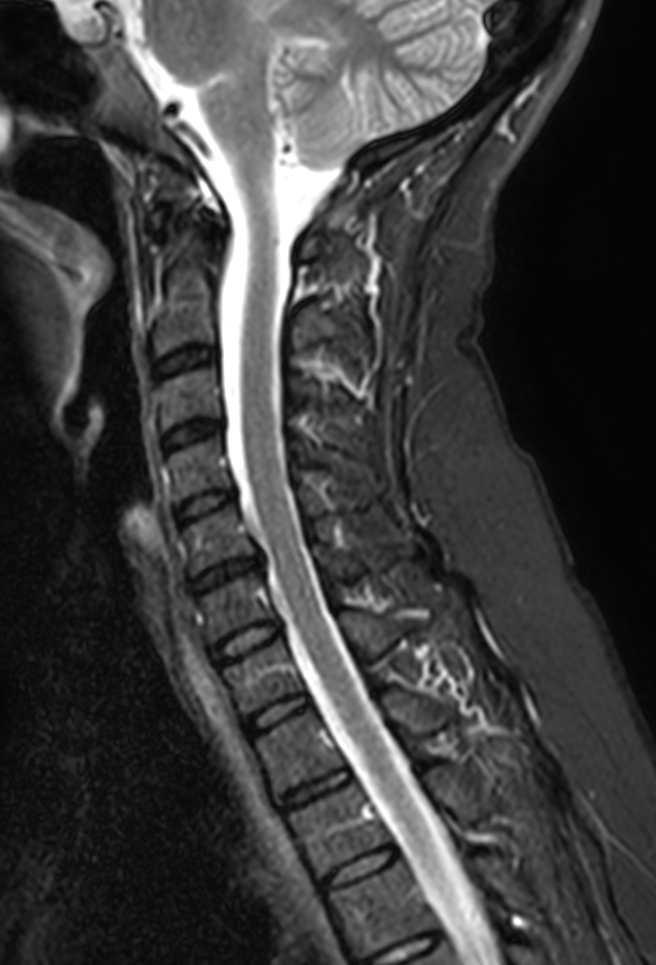

Cervical Spine on BlueSeal magnet

Spital Uster, Switzerland

Sagittal T2w TSE